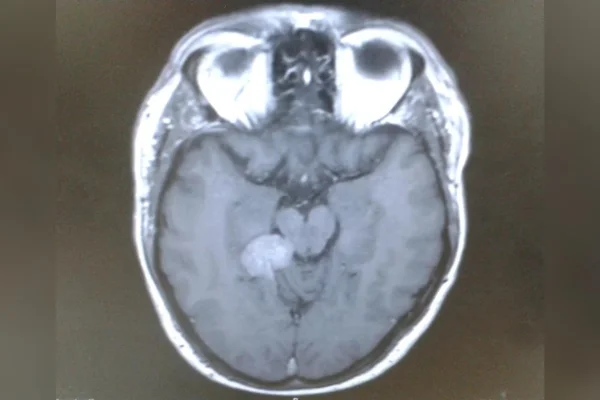

A confirmação veio em março de 2015. Após ser encaminhado a um neurocirurgião, Darren recebeu o diagnóstico de um meningioma tentorial em estágio inicial.

Trata-se de um tumor geralmente benigno e de crescimento lento, que se desenvolve a partir das meninges, as membranas que envolvem o cérebro. No caso dele, a lesão estava localizada na base do cérebro, em uma área considerada inoperável por causa dos riscos do procedimento.

Apesar de não ser canceroso, esse tipo de lesão pode causar uma série de sintomas ao pressionar estruturas cerebrais e nervos. Entre eles estão zumbido no ouvido, dores de cabeça, alterações na visão, perda auditiva, diminuição do olfato e dificuldade para engolir. Se não tratado, pode se tornar potencialmente fatal.

O meningioma é um tumor geralmente benigno, de crescimento lento, que se forma a partir das meninges, as membranas que envolvem o cérebro